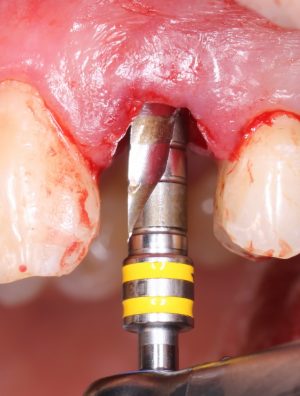

Прежде, чем приступить к аугментации (пластике) лунок зубов, мы подготовили лунки для имплантатов. В таких клинических случаях нет необходимости в использовании шаблона. Вместо этого, мы применяем общепринятые правила позиционирования и соблюдаем рекомендации производителя по хирургическому протоколу:

В процессе ирригации лунки промываются, что позволило нам еще раз подтвердить ранее сделанные выводы. С помощью аналогов имплантатов, входящих в хирургический набор Xive, мы проверили возможность стабилизации имплантатов в будущих лунках. Исходя из правил подбора и позиционирования имплантатов (я очень рекомендую почитать об этом здесь>>) мы остановились на Xive S диаметром 3,4 мм и длиной 13 мм.

Подготовка двух лунок для имплантатов занимает около 10 минут.

Затем уложили ксенографт. Особенностями Bio-Oss Collagen являются удобство адаптации, устойчивость к вымыванию и выдавливанию, поэтому мы просто уложили полученные ранее пирамидки вестибулярно относительно будущего имплантата, после чего прижали их с помощью уже упоминавшихся аналогов имплантата, входящих в хирургический набор имплантационной системы Xive (кстати, при работе с другими имплантационными системами для паковки графта в лунке можно использовать круглые остеотомы для синуслифтинга).

Установка имплантатов

По ряду уже упомянутых выше причин, для решения этой клинической задачи мы выбрали имплантаты Xive. Лунки для них мы уже приготовили. возможную первичную стабильность оценили. Имплантаты мы установили с усилием чуть больше 15-20 Нсм — такого крутящего момента более, чем достаточно, особенно если учесть, что временные коронки будут соединяться между собой.

Подробно о том, что такое крутящий момент и хирургический протокол можно прочитать здесь>> и тут>>, соответственно. Из-за использования специальных индивидуализируемых временных абатментов, имеющих только три положения, нам нужно позиционировать платформу имплантатов по граням. Это очень просто  — мы выводим вырез абатмента TempBase (он входит в комплект поставки) вестибулярно.

Установка имплантатов занимает около двух минут.